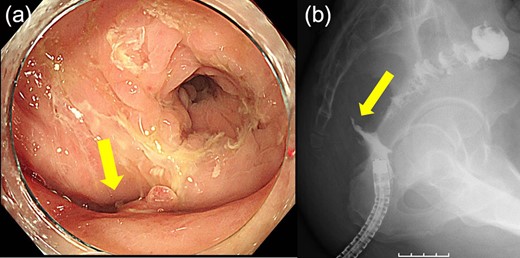

Case 2 was a 58-year-old man with a BMI of 30.3 kg/m2. Robot-assisted LAR and ileostomy was performed for lower rectal cancer over the past 2017 years, and a 1/2 circumferential fistula around the 6 o’clock direction was recognized on postoperative colonoscopy (Fig. 4). The patient was diagnosed as having a grade A anastomotic leakage without symptom because of the anastomotic leakage. He was discharged on POD 26 and was followed up on an outpatient basis. Contrast imaging performed simultaneously with endoscopic examination 6 months after the operation showed remarkable improvement of the abscess cavity, but it still remained (Fig. 5a and b). The anastomotic leakage improved 11 months after surgery (Fig. 6), but a polyp was found on the anal side 2 cm from the anastomotic site and was resected. Adenocarcinoma, pTX, ly0, v0, pHMX, and pVMX were diagnosed. The tumor was followed up because the depth of penetration, the deep stump, and the horizontal stump remained unknown (Fig. 7). Regarding the polypectomy site, no abnormality was found in the examination 8 months after resection of the polyp. Therefore, ileostomy closure was performed 18 months after the first operation (Fig. 8). Postoperatively, it took some time to improve the intestinal movement with paralytic ileus, but the patient was discharged 18 days after surgery. The Wexner score one month after closure was 18 points and still showed high anal dysfunction but the patient was under observation at the outpatient department.

(a) Endoscopic examination shows improvement of the suture failure and fistula formation (arrows). (b) Enema examination shows fistula (arrow).